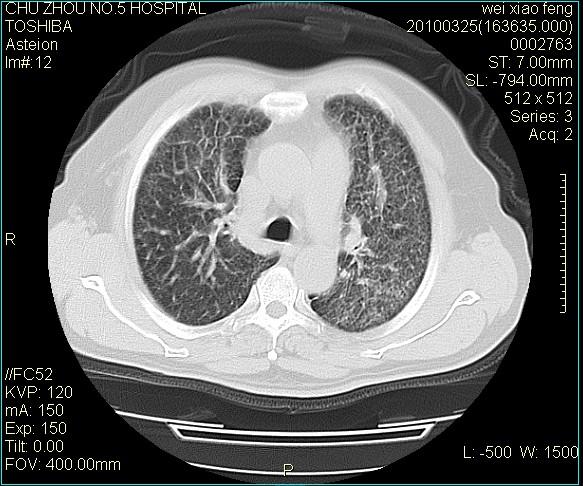

男,60岁,反复咳、痰、喘3月,加重3天。

双肺间质性改变。

考虑双肺血型潘散肺结核/

间质性肺炎伴间质纤维化!不排除伴有职业病!

双肺间质纤维化,双肺血型潘散肺结核。

考虑间质性肺炎伴间质纤维化。

右肺中叶结节影为原发灶,考虑右肺中叶周围型肺癌并淋巴道转移